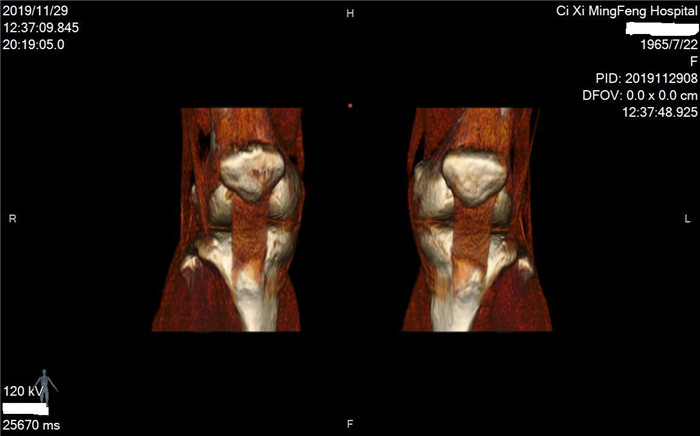

明峰CT搭載了領(lǐng)先的硬件技術(shù)平臺及系統(tǒng),強(qiáng)大的掃描能力可滿足臨床的各種要求,呈現(xiàn)更極致的細(xì)節(jié),為各臨床科室提供高品質(zhì)的圖像。薄層掃描,消除部分容積效應(yīng),提高各向同性。配合高分辨率算法,有助于細(xì)微結(jié)構(gòu)和形態(tài)學(xué)顯示。